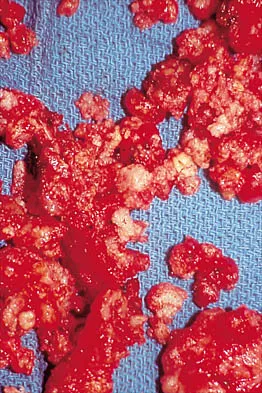

A 32-year-old woman has had pain and a visibly growing mass in the shoulder for 3 years but denies any history of trauma. Examination reveals a swollen, boggy shoulder mass. The AP radiograph and MRI scan are shown in Figures 20a and 20b. Figures 20c through 20e show a portion of the excised mass and the photomicrographs of the biopsy specimen. What is the most likely diagnosis?